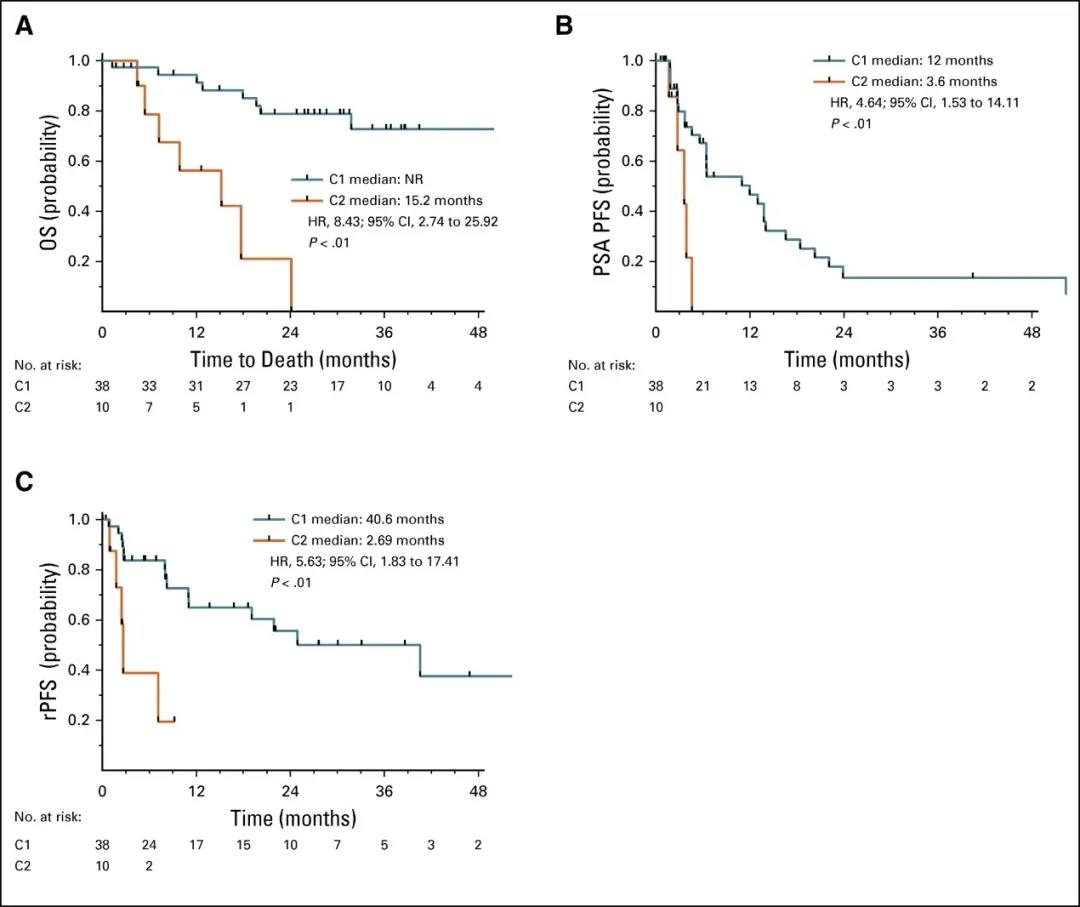

几乎所有接受雄激素受体(AR)信号抑制剂(ARSI)治疗的前列腺癌男性都会通过多种机制产生耐药性,包括 AR 通路的激活,AR 基因结构改变、AR 剪接变体(AR...

1 前列腺癌流行病学特征随着中国经济水平提高、人民生活水平改善和人均寿命延长,中国前列腺癌的发病率呈显著上升趋势,正逐步成为影响中国中老年男性健康的重要疾病[1]...